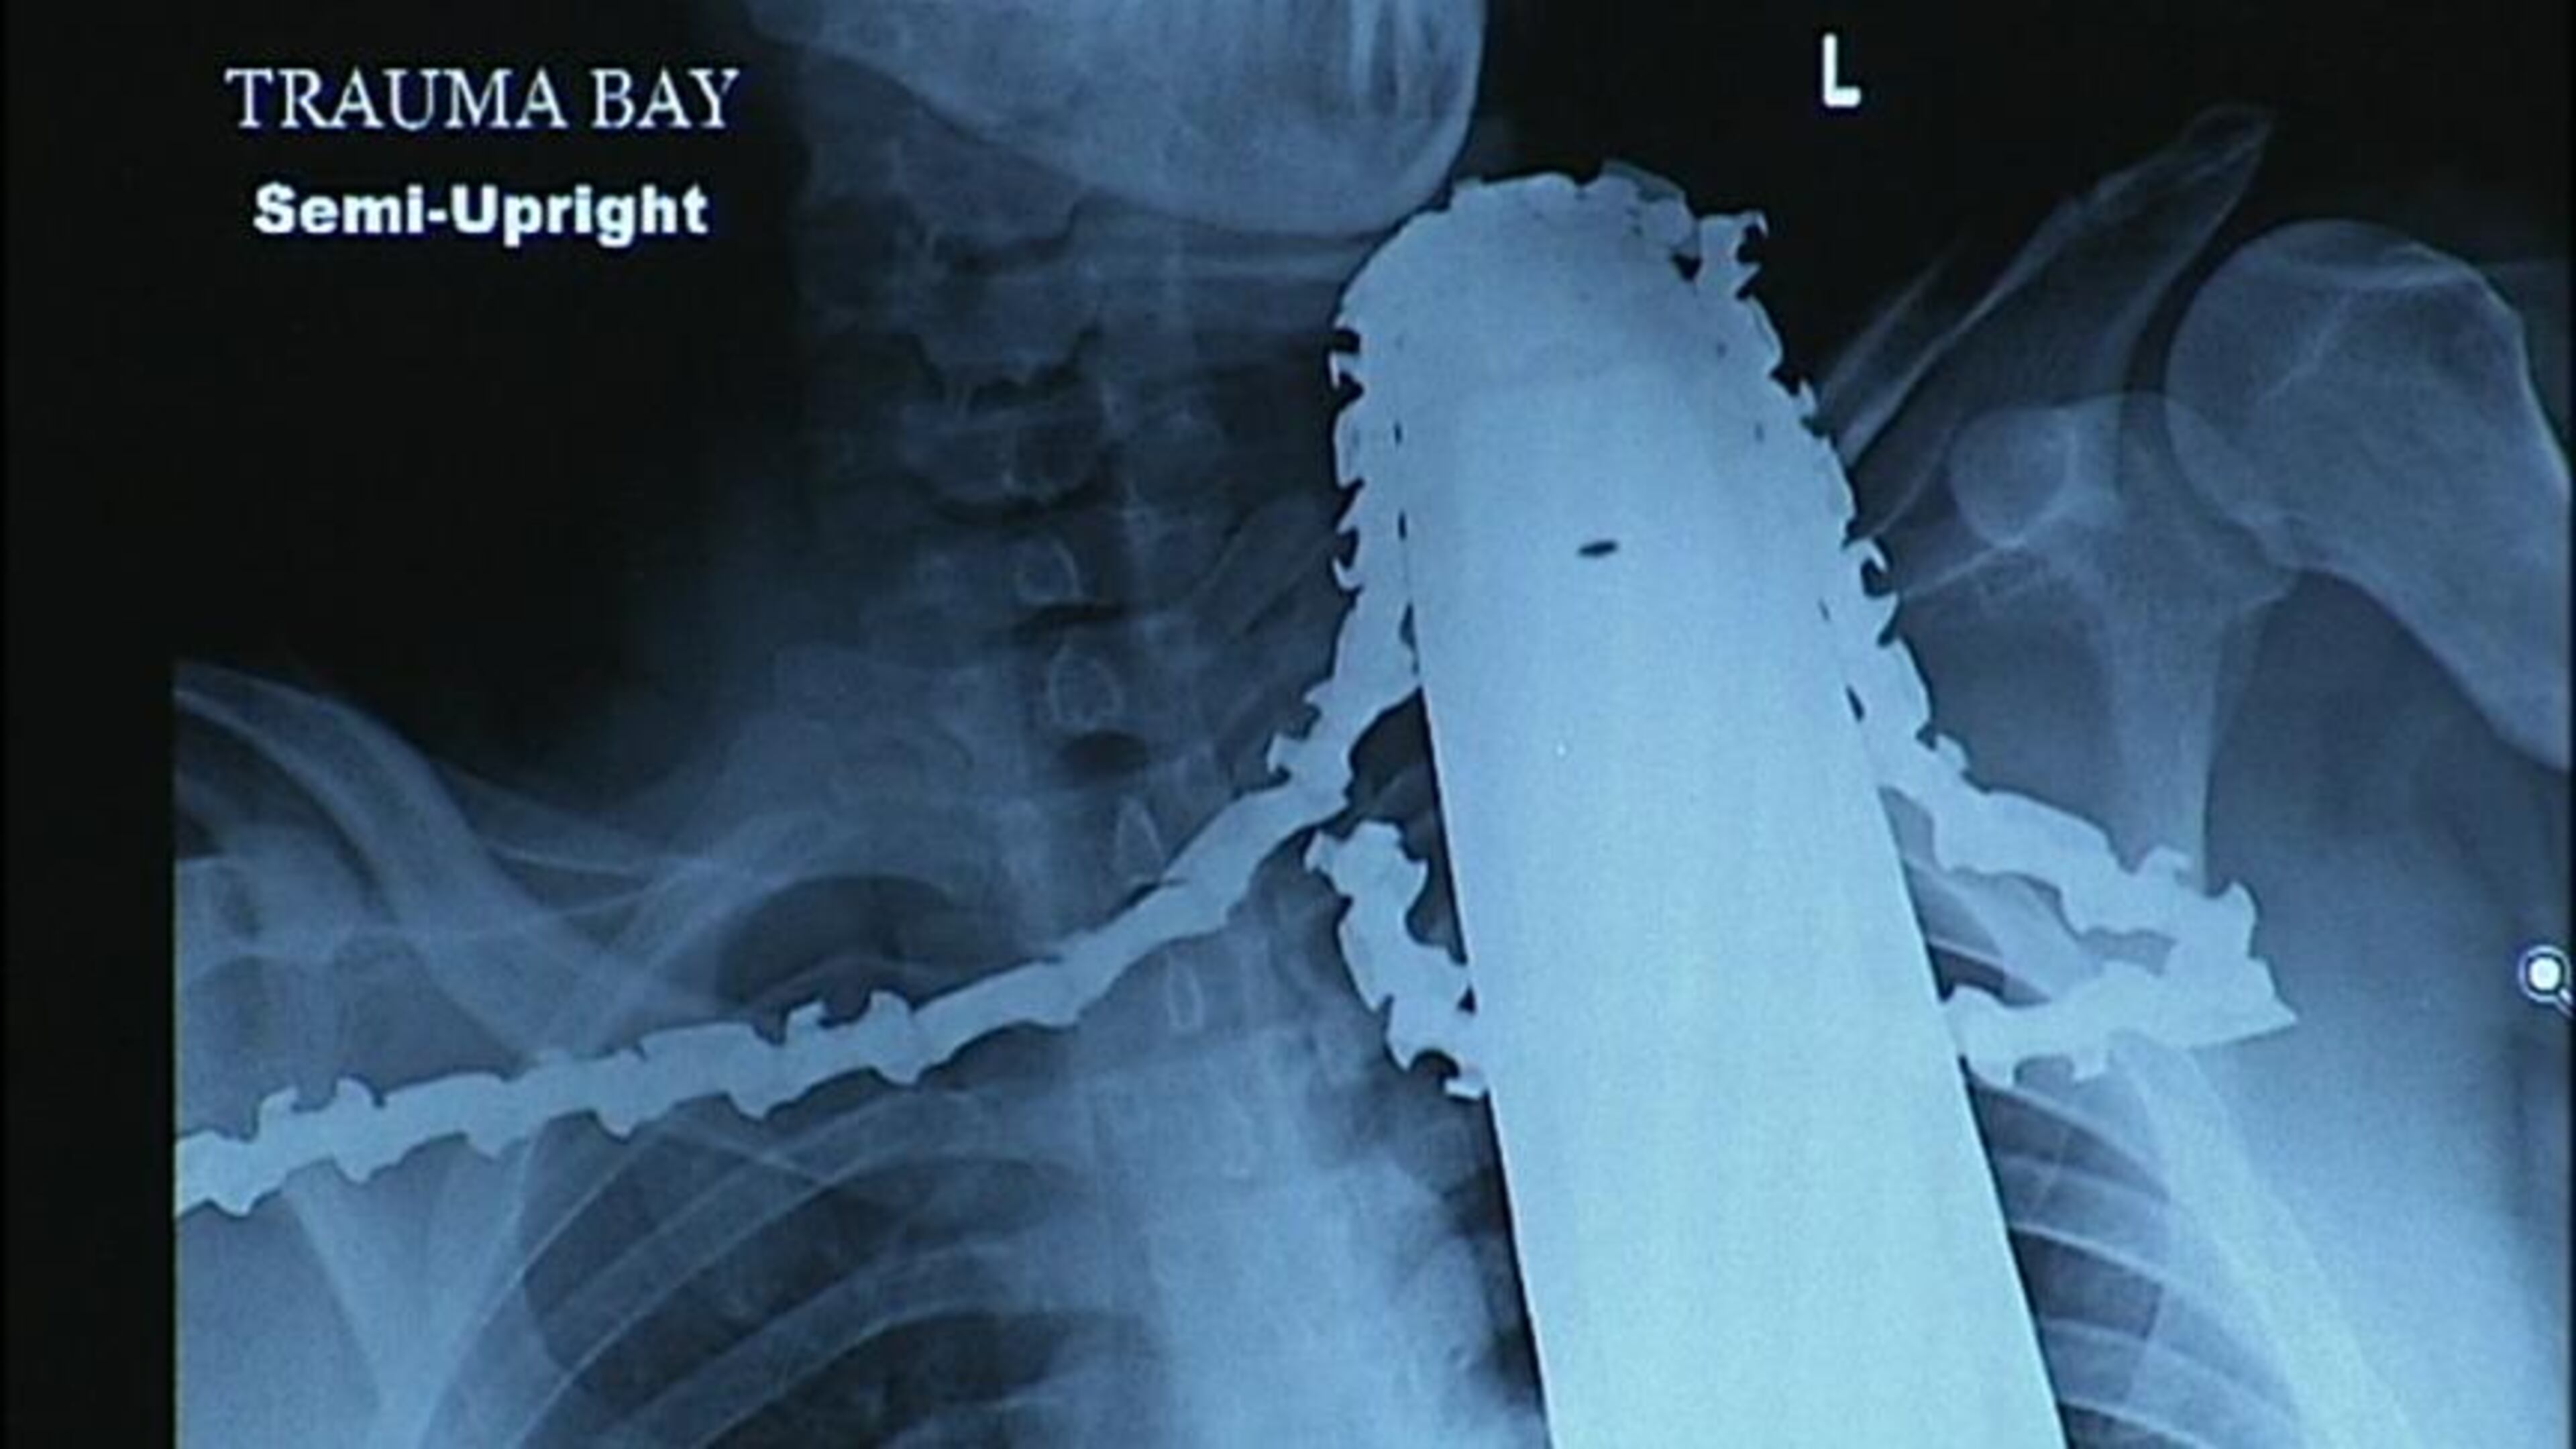

A man continues to recover on Tuesday after he was rushed to a hospital in Pittsburgh on Monday with a chainsaw lodged in his neck following a tree-cutting accident in Ross Township, Pa.

James Valentine, an employee with Adler Tree Service, was working in a tree when his chainsaw kicked back and hit him in the neck, police said. The accident happened about 2:30 p.m.

Medics left the chain saw in Valentine’s neck as they transported him to the hospital.